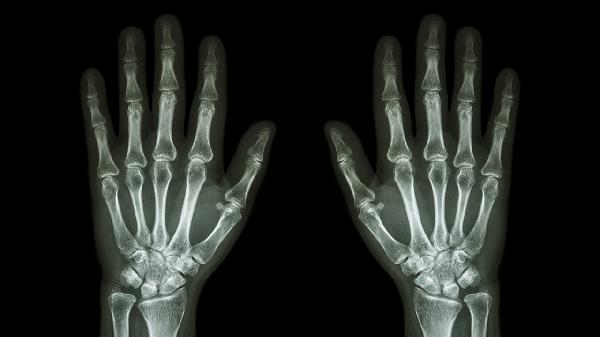

若X线检查显示关节骨折移位超过2毫米或肌腱完全断裂,需行切开复位内固定术。术后需石膏固定4-6周,配合康复训练恢复抓握功能。陈旧性腱鞘炎反复发作者可考虑腱鞘松解术。